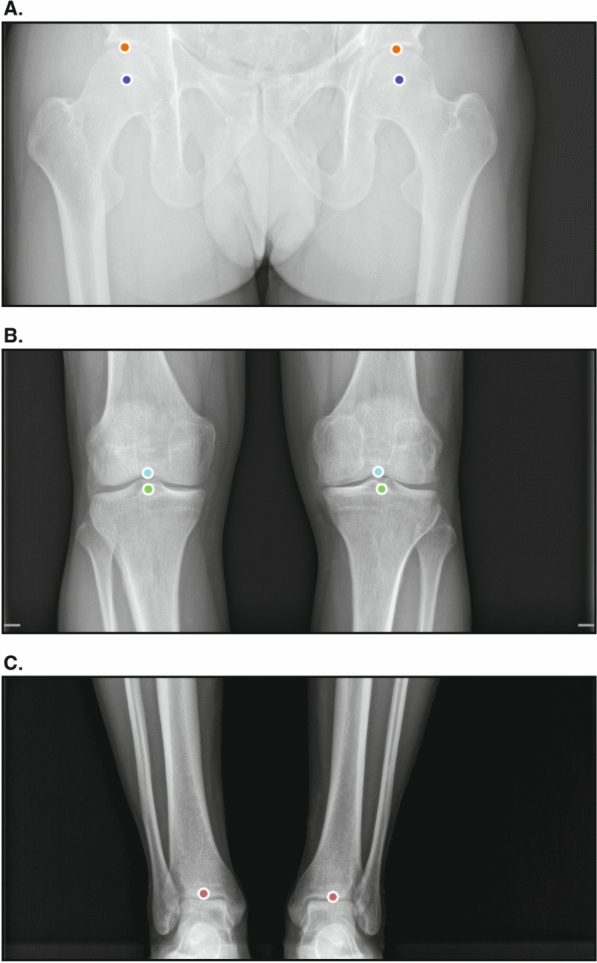

Methods: A retrospective analysis was conducted on a dataset comprising consecutive anteroposterior full-leg standing radiographs obtained from four imaging institutions. Key anatomical landmarks to define the hip-knee-ankle angle, pelvic obliquity, leg length, femoral length, and tibial length were annotated independently by two expert musculoskeletal radiologists and served as the ground truth. The performance of the AI was compared against these reference measurements using the mean absolute error, Bland-Altman analyses, and intraclass correlation coefficients.

Results: A total of 175 anteroposterior full-leg standing radiographs from 167 patients were included in the final dataset (mean age = 49.9 ± 23.6 years old; 103 women and 64 men). Mean absolute error values were 0.30° (95% confidence interval [CI] [0.28, 0.32]) for the hip-knee-ankle angle, 0.75 mm (95% CI [0.60, 0.88]) for pelvic obliquity, 1.03 mm (95% CI [0.91,1.14]) for leg length from the top of the femoral head, 1.45 mm (95% CI [1.33, 1.60]) for leg length from the center of the femoral head, 0.95 mm (95% CI [0.85, 1.04]) for femoral length from the top of the femoral head, 1.23 mm (95% CI [1.12, 1.32]) for femoral length from the center of the femoral head, and 1.38 mm (95% CI [1.21, 1.52]) for tibial length. The Bland-Altman analyses revealed no systematic bias across all measurements. Additionally, the software exhibited excellent agreement with the gold-standard measurements with intraclass correlation coefficient (ICC) values above 0.97 for all parameters.